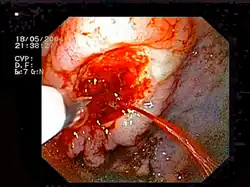

Krwawienie

Do tego bardzo rzadkiego powikłania dochodzi u pacjentów z zaburzeniami krzepnięcia krwi, a także podczas niektórych procedur zabiegowych, takich jak usuwanie polipów czy rozszerzanie zwężeń.